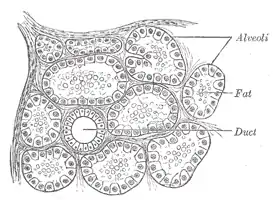

Human submaxillary gland. At the right is a group of mucous alveoli, at the left a group of serous alveoli. Section of portion of mamma.

Section of portion of mamma.